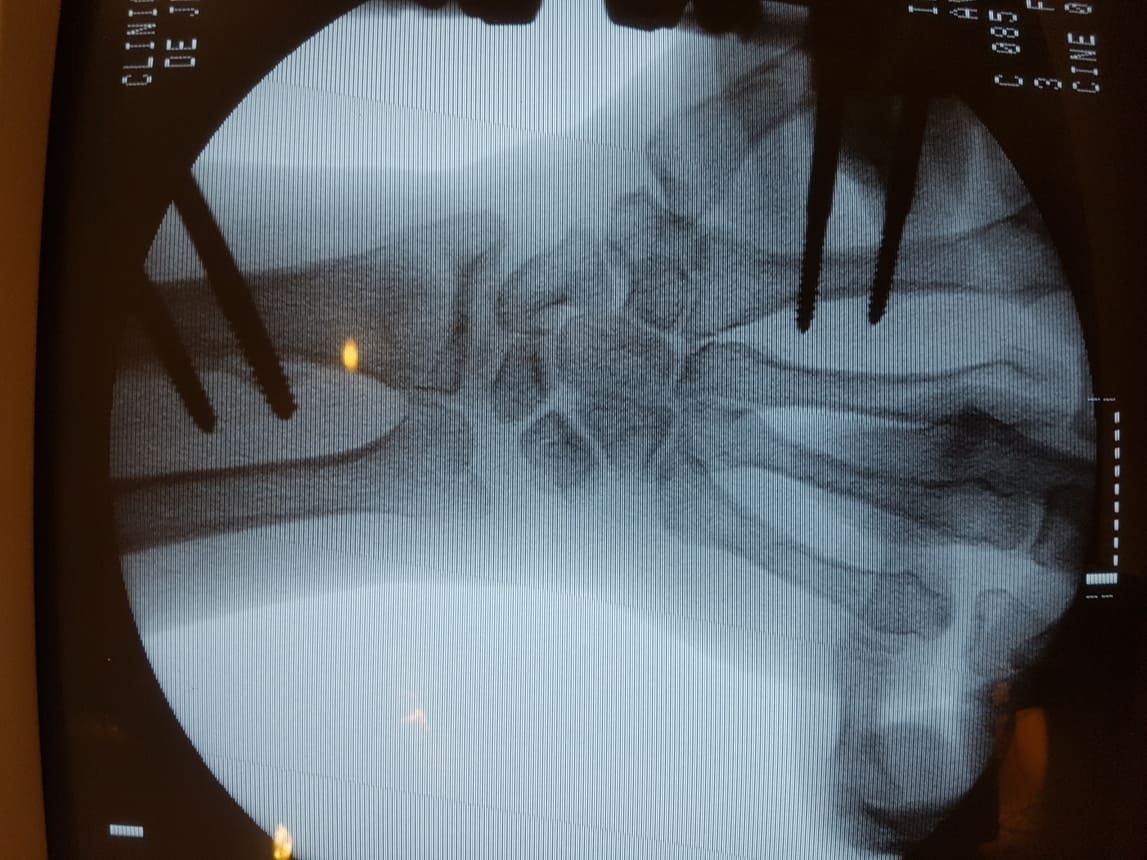

TRATAMIENTO DE FRACTURAS - GALERÍA DE IMÁGENES

Fractura de tobillo